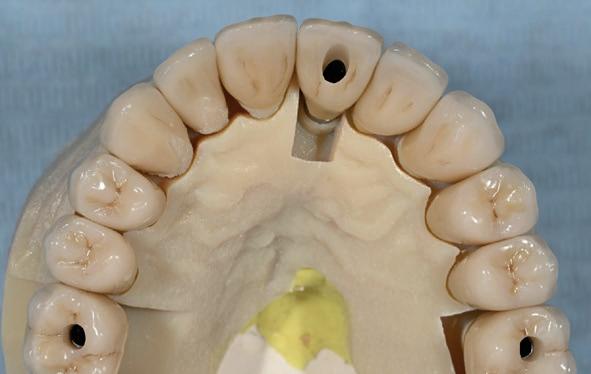

13. Techniekmodel

plaatsing van de restauraties werden zowel de tandboog als de tandstand in de bovenkaak gecorrigeerd (afbeelding 13-15).

Aansluitend werd de onderkaak volgens hetzelfde principe gerehabiliteerd, resulterend in een stabiele, functionele en esthetisch gebalanceerde occlusie (afbeelding 16-17).

Reflectie: samenwerking als sleutel

Deze casus benadrukt de rol van heldere communicatie en frequente evaluatie binnen interdisciplinaire samenwerking. In de eerste fase werd gezamenlijk besloten welke elementen te behouden waren en waar implantaten noodzakelijk waren voor een opti-

male prothetische uitkomst. Tijdens de restauratieve fase speelde de restauratief behandelaar een actieve, dirigerende rol door continu het ontwerp bij te sturen in nauwe samenwerking met het tandtechnisch laboratorium. Door regelmatige evaluatiemomenten, zoals na vervaardiging van de mock-up, werd de prothetische planning verfijnd. Tevens vond er intensieve gedeelde besluitvorming plaats tussen restauratief behandelaar en patiënt, waardoor individuele wensen optimaal werden geïntegreerd in het definitieve behandelresultaat.